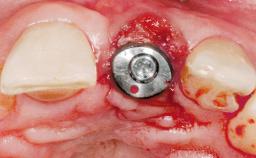

Immediate Placement of an Implant in a Maxillary Right Central Incisor Site

A 30-year-old female patient was referred to the office for the treatment of tooth 11. Her chief concern at the initial visit was to inquire, “Why is my tooth pink?” Upon clinical examination, it was determined that tooth 11 had a previous history of trauma and that the clinical crown had become noticeably pink in color as a result of internal resorption. This diagnosis was confirmed radiographically, indicating a large radiolucency involving the central and distal portions of the clinical crown. It was determined that restoration of this tooth was not possible, and that extraction was indicated. The presence of a mid-line diastema, which the patient wanted to reproduce, directed the treatment plan for tooth replacement utilizing a dental implant.

Placement Protocol Immediate implant placement

Socket Morphology Single-root socket

Socket Integrity Sufficient, with intact bone walls

Bone Augmentation Horizontal|Simultaneous

Augmentation Materials Autogenous chips|Membrane